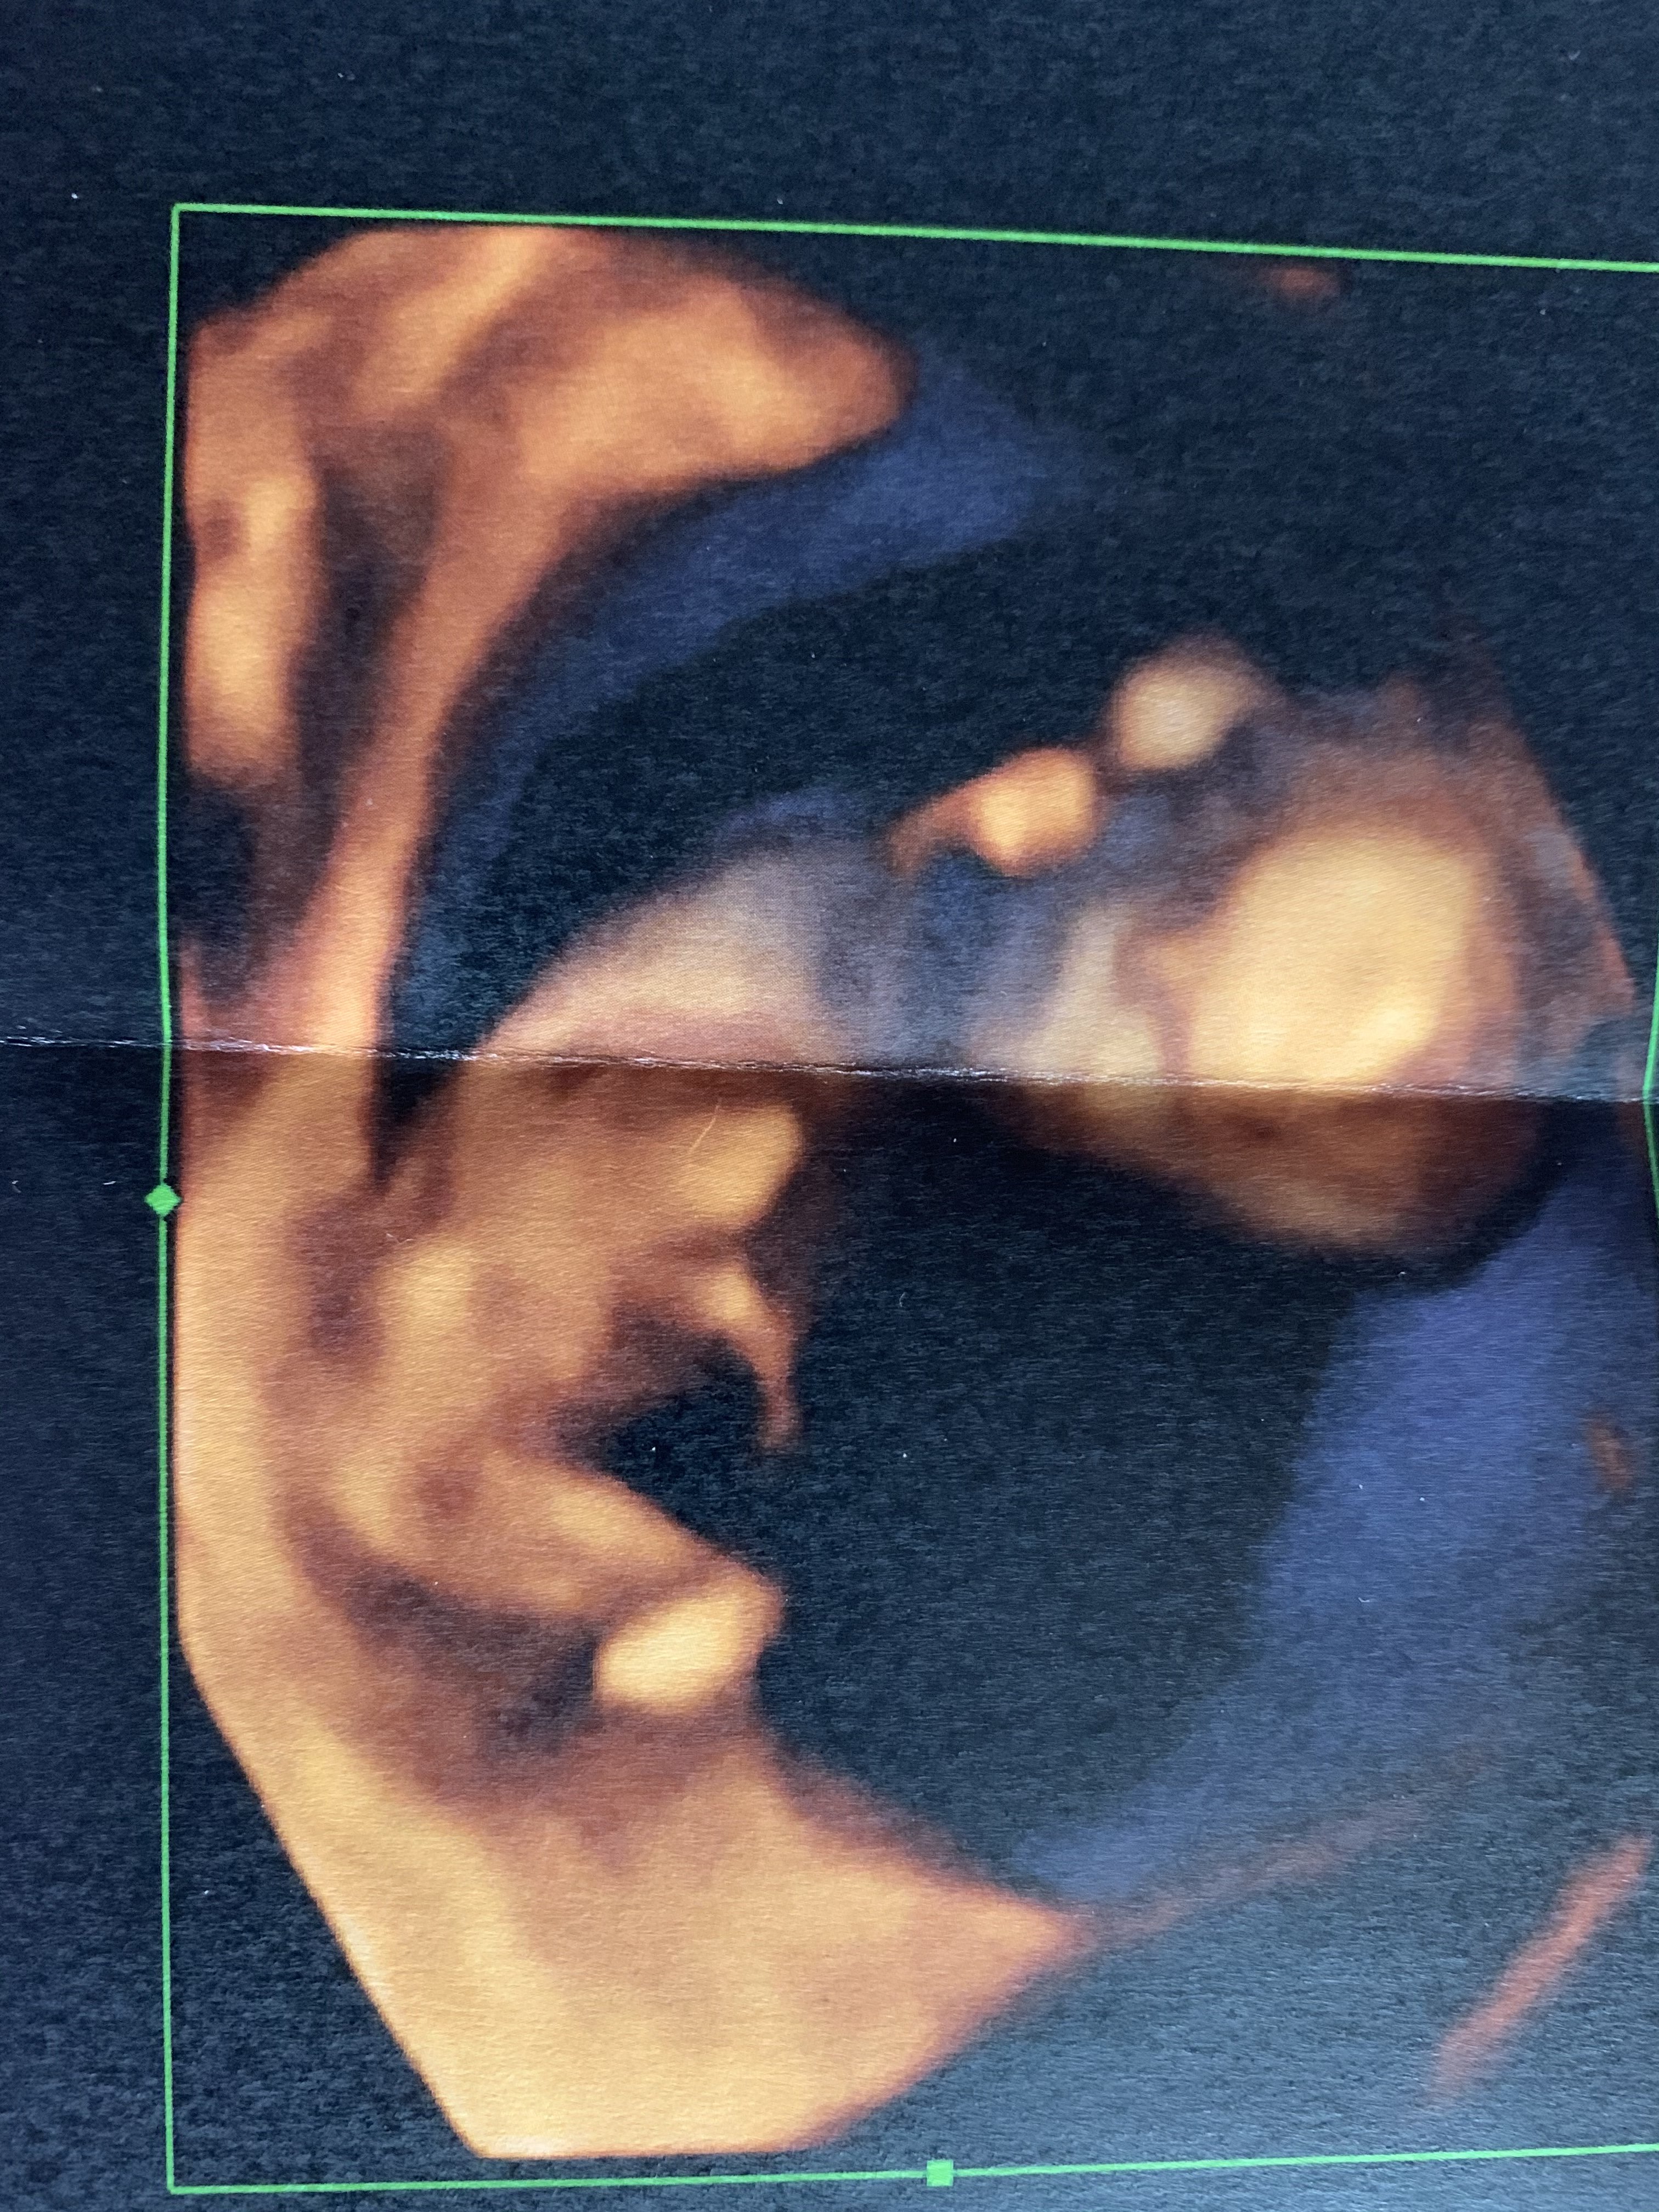

No właśnie ostatnio w prawie 15tygodniu byłam u lekarza i nawet nie starał się sprawdzić płci (stary sprzęt) i muszę czekać do połówkowych 😕 tutaj najbardziej wiać co jest pomiędzy nogami,ale i tak nadal nie wiem.Dla was na kogo to wyglada? Jest to moje pierwsze dziecko i sama nie wiem... od początku czułam dziewczynkę i każdy też na nią stawia,lekarz pierwsze co to stwierdził babę a potem,ze jednak coś wystaje i chyba chłop.. Dla porównania dodam ze osoba 2 lata temu była u tego samego lekarza i odrazu w tym samym czasie trwania ciąży stwierdził chłopa i potwierdziło się,a u mnie sam nie wie.

DB743194-3C97-4619-B939-A751914B43FF.jpeg